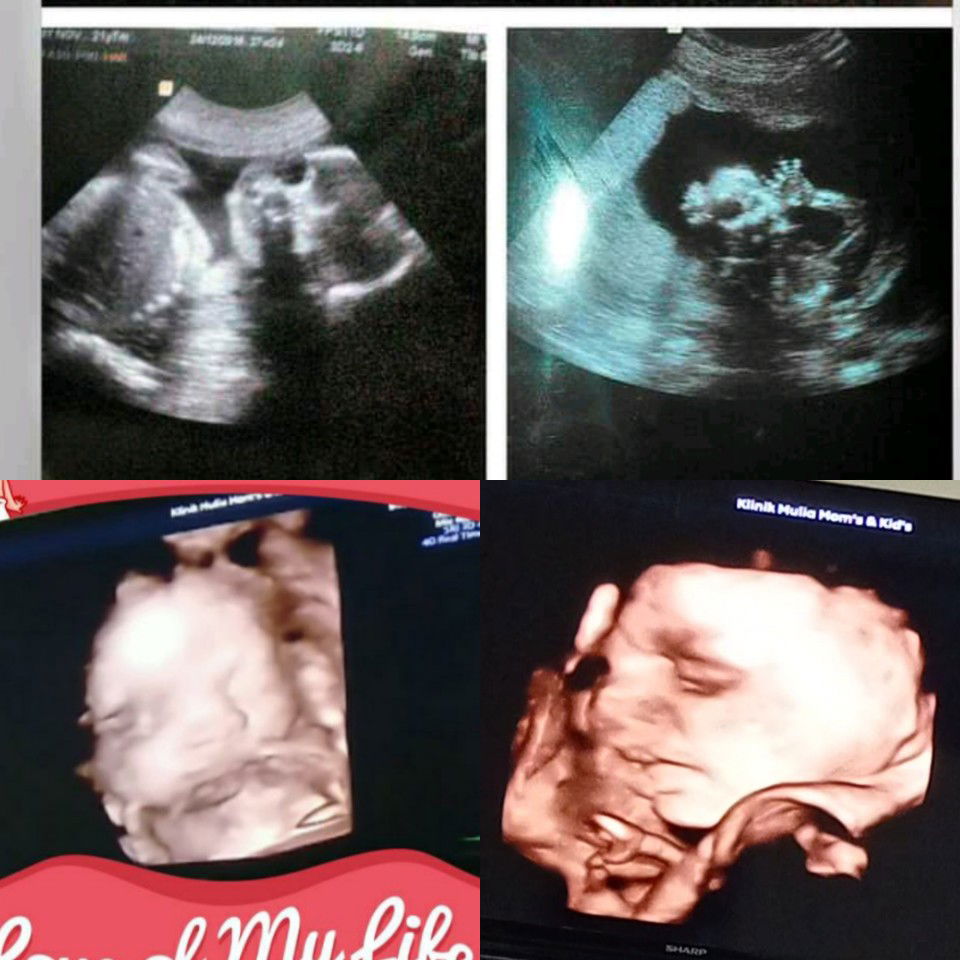

Bunda2 yg hpl Desember kira2 udah pda masuk panggul belum baby nya ? hbis pulang kontrol 37w si adek belum masuk panggul pdhal sudah yoga & jalan2 bismillah masih ada wktu buat usaha biar adek masuk panggul doain ya bund semoga bunda2 yg nggu adek masuk panggul di segerakan yah kya aku amiiiin 😘 #seriusnanya #bantusharing #ingintahu #pleasehelp